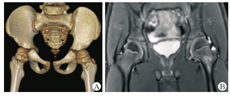

本研究中,17例干骺端局部骨质破坏,大小不一,诊断为Brodie脓肿,其中7例表现为干骺端较大的类圆形或者椭圆形破坏灶,首诊通过X线检查就能发现,不易漏诊;10例表现为紧贴干骺端骨皮质微小破坏灶,局部伴或不伴骨膜反应,可伴有骨质硬化,X线检查表现不明显,需借助CT扫描重建识别,同时需与骨样骨瘤相鉴别。3例患儿胫骨干局部骨皮质成梭形增生肥厚,首发症状以触及小腿肿物就诊,无明显疼痛,诊断为Garré骨髓炎。余2例股骨颈局部骨皮质破坏表现为"虫蚀样"破坏伴局部硬化属于特殊类型感染(典型病例见图5)。

本研究中,股骨近端感染的患儿包括股骨粗隆下、粗隆间以及股骨颈,通常以跛行为首发症状。对于微小的感染灶,X线检查容易漏诊,易被单纯考虑为髋关节滑膜炎而延误治疗。但CT和MRI可以清楚地辨别,尤其是MRI可以清晰地显示周围软组织和骨髓的水肿情况及髋关节积液是否增加,对早期发现、明确诊断起到积极作用。